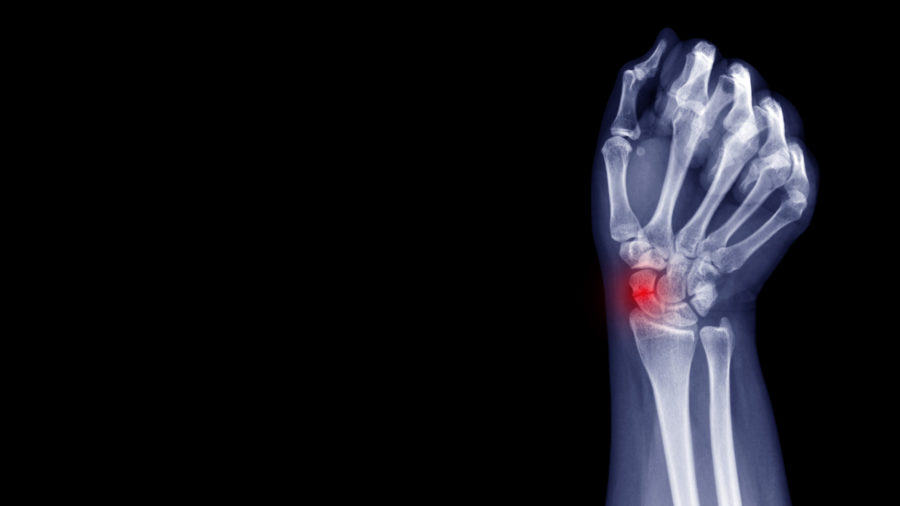

The Scaphoid is one of the eight carpal bones that make up the wrist. It is the commonest carpal bone to be fractured and is more common in young men. The injury occurs often from a fall onto an outstretched hand, sports related injury or a sudden torque injury from power tools. Scaphoid fractures tend to cause swelling and pain on the radial (thumb) side of the wrist and can often be overlooked as a wrist sprain. Despite seeking medical attention, there is a high rate of missed diagnoses due to many fractures not easily seen on initial X-Ray. The scaphoid has an unusual blood supply which can affect it’s healing. It is the key bone that stabilises the wrist and if a fracture is missed or does not heal, this can lead to collapse and arthritis in the wrist at an early age. If you have pain on the radial side of the wrist following an injury that continues for longer than a week, you should seek medical attention.

If initial X-Rays do not show the fracture but there is persistent pain and swelling in the radial side of the wrist, your doctor may ask you to have a CT or MRI scan to give more detailed imaging of the area. This can identify occult scaphoid fractures and the amount of displacement or other injured structures in the area such as distal radius fractures, scapholunate ligament injuries, trapezium fractures or other ligamentous injuries. This helps guide you and your doctor’s choice of treatment.